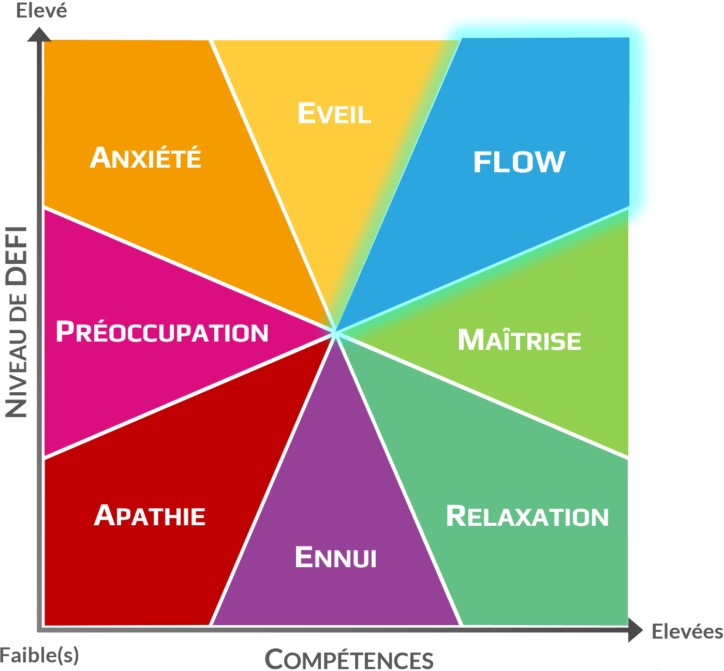

Ennui fréquent (Dispersion, désœuvrement, frustration, Intérêt, impatience, hyperfocalisation, abandon, ennuie)  A la recherche difficile de l’expérience optimale (flow), créé souvent chez nous avec l’hyperfocalisation  Cliquez pour agrandir |

► Malgré

un intérêt pour tout ce qui traverse leur esprit, ils se

dispersent puis s’essoufflent, et tombent souvent dans des

périodes inactives (hypo-actives) où l’ennui et la frustration

prédominent. – Les pensées vont trop vite dans leur tête pour en attraper une, ou bien elles sont trop nébuleuses pour agir. – Ils ne trouvent pas assez de plaisir ou de motivation dans leurs relations et activités quotidiennes ainsi que les tâches incontournables d’un projet. → Alors ils plongent dans l’ennui que les vrais hyperactifs vont souvent éviter en continuant à se disperser, alors que les hypoactifs vont opter pour le désœuvrement. – Beaucoup développent une intolérance à leur frustration qui se concrétise en énervement interne ou externe, pour certains en colère et pour d’autres en rumination interne voire en déprime chronique. ► Ils n’ont pas la capacité à maintenir leur motivation pour leurs projets sur une longue période. Ils perdent beaucoup d’énergie dans l’ennui avec, soit une cogitation mentale incessante, soit une hyperactivité non productive, qui leur procure des émotions négatives. – Celles-ci peuvent être la peur du rejet ou de l’humiliation, des pensées de critiques ou ressentiment envers les autres, de la culpabilité de ne rien faire ou de perdre son temps, etc.). – Ces pensées sont très fluctuantes et peuvent être positives ou neutres en début de vie d’adulte (Day Dreaming), mais d’échecs en échecs (de leurs points de vue du moins), elles deviennent souvent fixes et négatives et peuvent se transformer en névroses en prenant de l’âge. ► Ils alternent avec une impatience exagérée ou une passion extrême quand ils se connectent enfin à quelque chose, avec une hyper focalisation (voir symptôme suivant), un plaisir immédiat, ou une promesse de solution pour leur avenir, qui peut commencer par une frénésie de recherche sur le Web par exemple. – Ils veulent des résultats rapides et enchainent les illusions et les désillusions, au lieu de passer en mode réalisation qui leur apporterait de vraies satisfactions. – Certains se définissent un objectif quasi obsessionnel qui peut consister à reprendre des études laborieuses pour atteindre le métier qui leur semble idéal. – Mais on verra plus loin qu’ils peuvent créer régulièrement un état de flux créatif et concret à la fois (flow), qui peut se matérialiser par une l’hyperfocalisation productive fréquente, si les niveau de compétence et de défis sont tous les deux bons ► Enfin, beaucoup développent un auto-sabotage régulier, c’est à dire qu’ils abandonnent d’un coup ce qui les a captivés pendant des heures, parfois des jours ou des mois, même si c’est sur le point d’aboutir (avant l’examen par exemple), même s’ils ont eu ce qu’ils voulaient, comme si le but une fois atteint perdait d’un coup son intérêt de départ. – Certains ne fonctionnent bien qu’en mode gratuité ou individuel et s’arrêtent quand arrive un enjeu financier ou relationnel, même s’ils ont besoin d’argent et de relations humaines. – D’autres abandonnent quand les phases créatives de leur projet sont terminées, en refusant de passer en mode réalisation pour mener à bout leurs idées. ► Dans les relations amoureuses ou amicales, cela peut se concrétiser par une insatisfaction systématique car le processus de séduction ou l’espoir de se sentir mieux à deux est bien plus gratifiant que la relation elle-même quand elle se réalise. – Dans le domaine professionnel, ils ont besoin de nouveaux horizons et pratiquent souvent la politique de la terre brulée, où ils ne veulent même pas capitaliser sur ce qui les a passionnés précédemment. – Cela peut poser problème car ils doivent à chaque fois repartir à zéro avec comme conséquence une stagnation ou une régression des revenus financiers. |